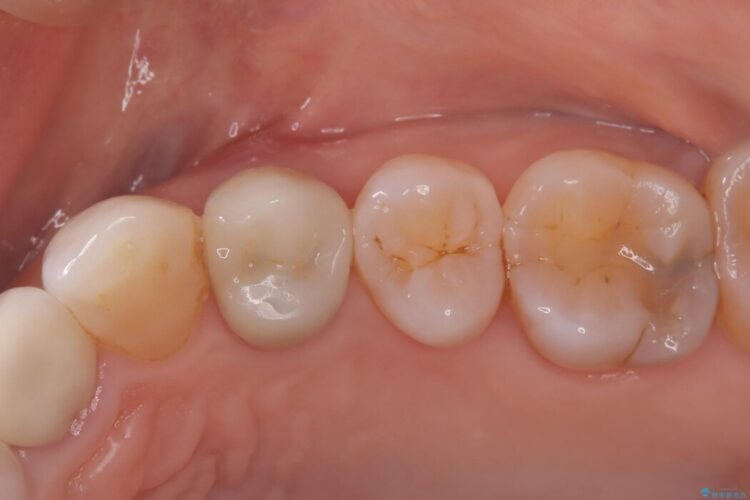

自然な見た目のセラミックインレーで精密に修復

自然な見た目のセラミックインレーで精密に修復 ビフォー 自然な見た目のセラミックインレーで精密に修復 アフター

右上5番に小さな穴があるとご相談にいらした患者様です。